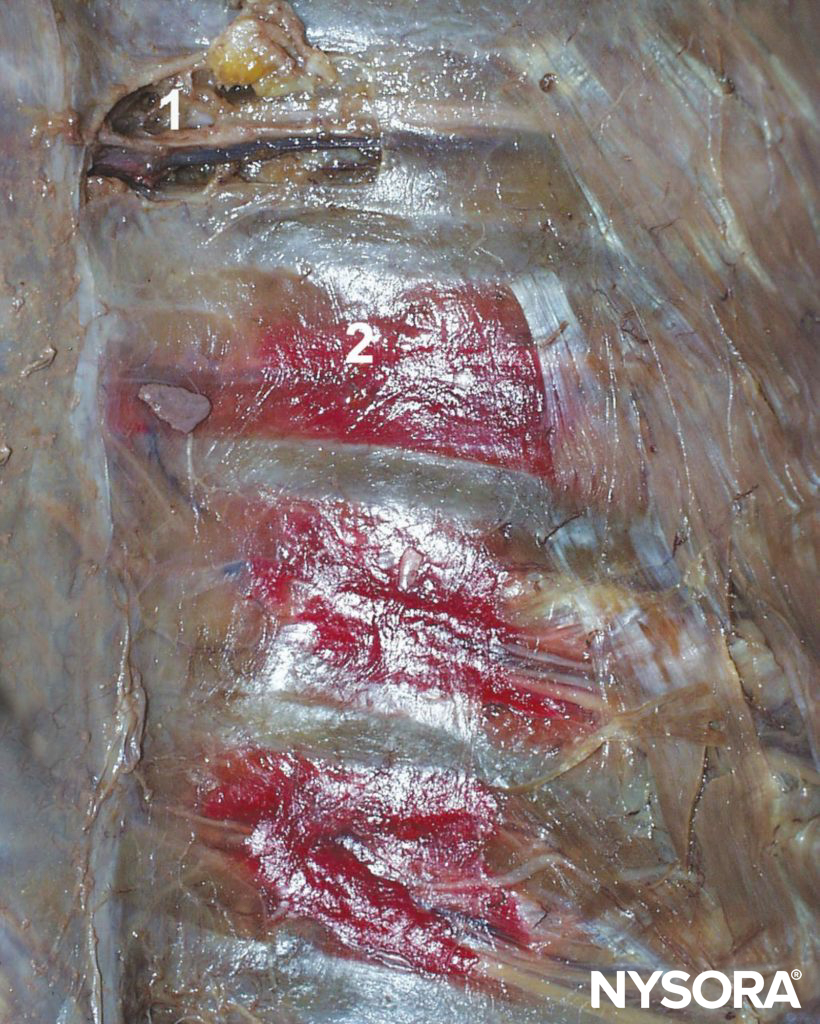

Carrying both sensory and motor fibers, the ICN pierces the posterior intercostal membrane about 3 cm (in adults) distal to the intervertebral foramen to enter the subcostal grove where it, for the most part, continues to run parallel to the rib, although branches may often be found anywhere between adjacent ribs. Its course within the thorax is sandwiched between the parietal pleura and innermost intercostal (intercostalis intimus) muscles and the external and internal intercostal muscles (Figures 3 and 4). Just anterior to the midaxillary line, it gives off the lateral cutaneous branch. As the ICN approaches the midline, it turns anteriorly and pierces the overlying muscles and skin to terminate as the anterior cutaneous branch.

Figure 3 Intercostal nerves (accompanied by intercostal artery and vein) shown in the intercostal sulcus as seen from within the open chest cavity in a cadaver. The red dye illustrates spread of solutions injected into the intercostal sulcus during intercostal block. 1. Intercostal nerve. 2. Distribution of the dye after injection into the intracostal sulcus.

ICNB blocks the ipsilateral sensory and motor fibers of the ICNs. Local anesthetic solution injected into the subcostal groove spreads both distally and proximally; some of the injectate may enter paravertebral space as well. (see Figure 3).